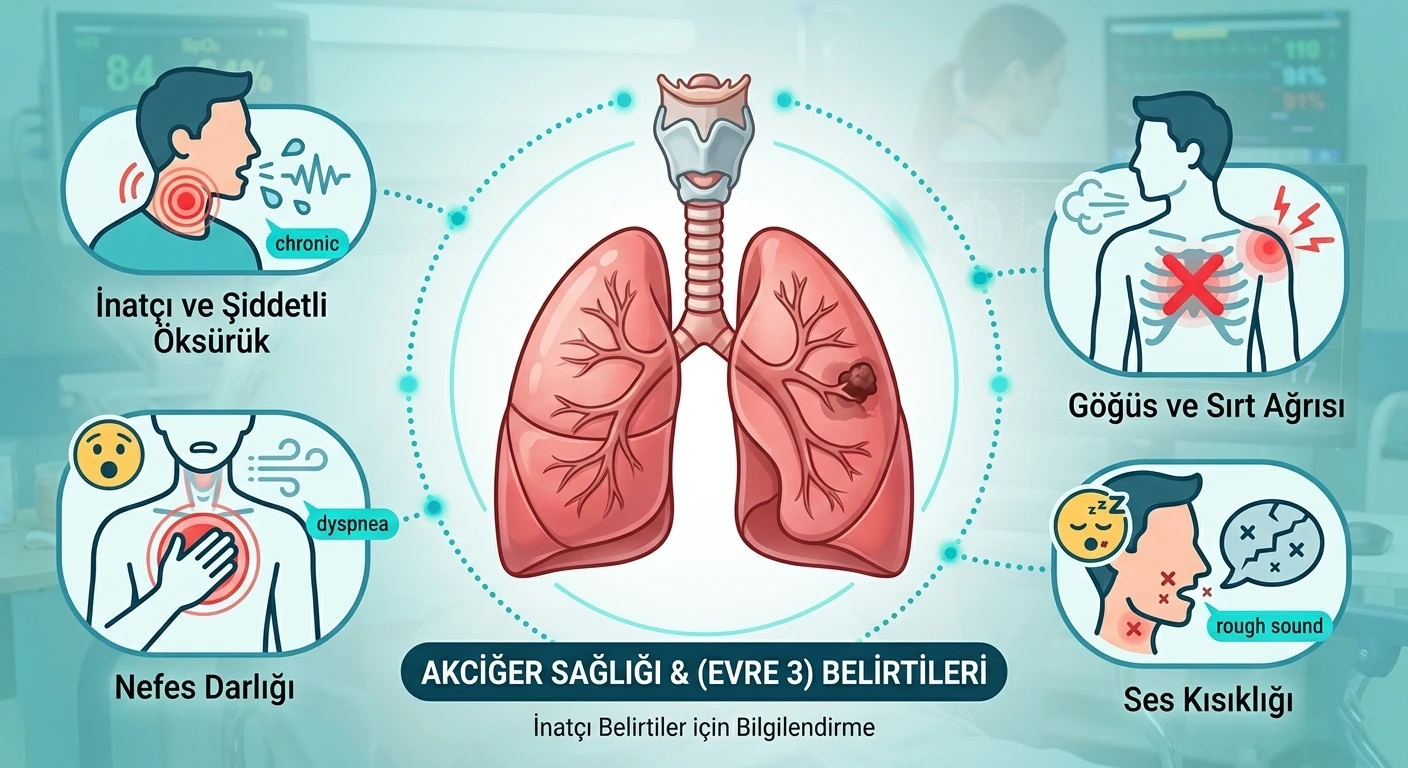

EVRE 3

EVRE 3

Tümör göğüs kafesi içindeki mediyasten lenf bezlerine yayılmıştır.